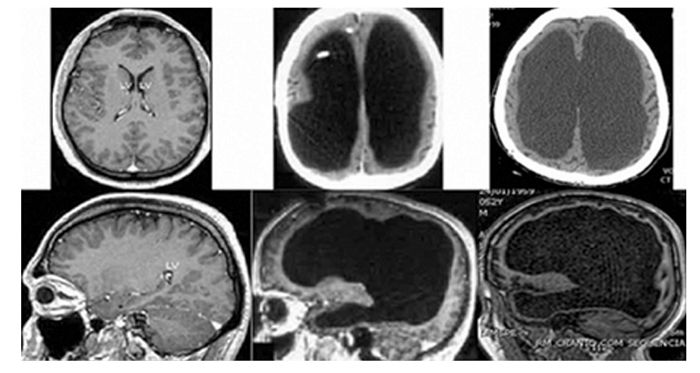

존 로버는 증상의 원인을 파악하기 위해 뇌 CT를 촬영하게 된다. 그러나, 그는 촬영 결과를 보고 소스라치게 놀라게 된다.

학생의 두개골 안에는 뇌가 없었던 것이다. 뇌가 있어야 할 부분에는 가득찬 뇌척수액만이 있었다.

극도로 심한 뇌수종(Hydrocephalus)으로 인해 이와 같은 현상이 일어나게 된 것이었다.

정상인의 뇌의 무게는 약 1.5kg 정도지만, 그 학생의 머리에는 약 300g 남짓의 뇌척수액과 이를 감싸고 있는 얇은 막만 존재했다. 사실상 뇌가 없는 상태였다.

그 결과 전체 환자 중 60명이 뇌의 95%가 없는 상태였다. 그중 절반은 심각한 장애를 앓고 있었지만, 나머지 절반은 지능지수 100이 넘는 정상인이었다.